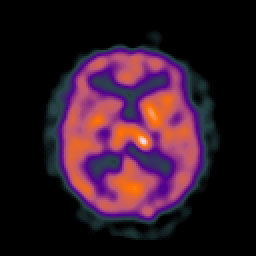

Tour 1: Next/Previous/Start: These images show typical findings in AIDS dementia: patchy hypoperfusion with a multifocal distribution which tends to be seen prominently in the frontal lobes. Compare with normal. Defects in cerebral perfusion have been previously reported in HIV positive individuals by single photon emission computed tomography (SPECT)[Masdeu, 1989 ][Pascal, 1991 ][Pohl, 1988 ][Holman, 1992 ][Schielke, 1990]. The anatomic and clinical significance of these findings, however, has remained uncertain. Because previous studies have shown that AIDS dementia complex (ADC) is associated with both functional defects and structural evidence of brain volume loss, we spatially matched (registered) the functional and structural data to assess the extent to which observed perfusion defects were "real", that is, represented low tracer uptake from structurally normal brain. The image datasets shown here are sampled along the same plane of view, to permit the direct comparison of SPECT and MR images in ADC. This type of analysis shows that there are functional defects (ie perfusion defects) in areas that appear non-atrophic. These are perhaps sites of early damage in which the structural images are still relatively normal.